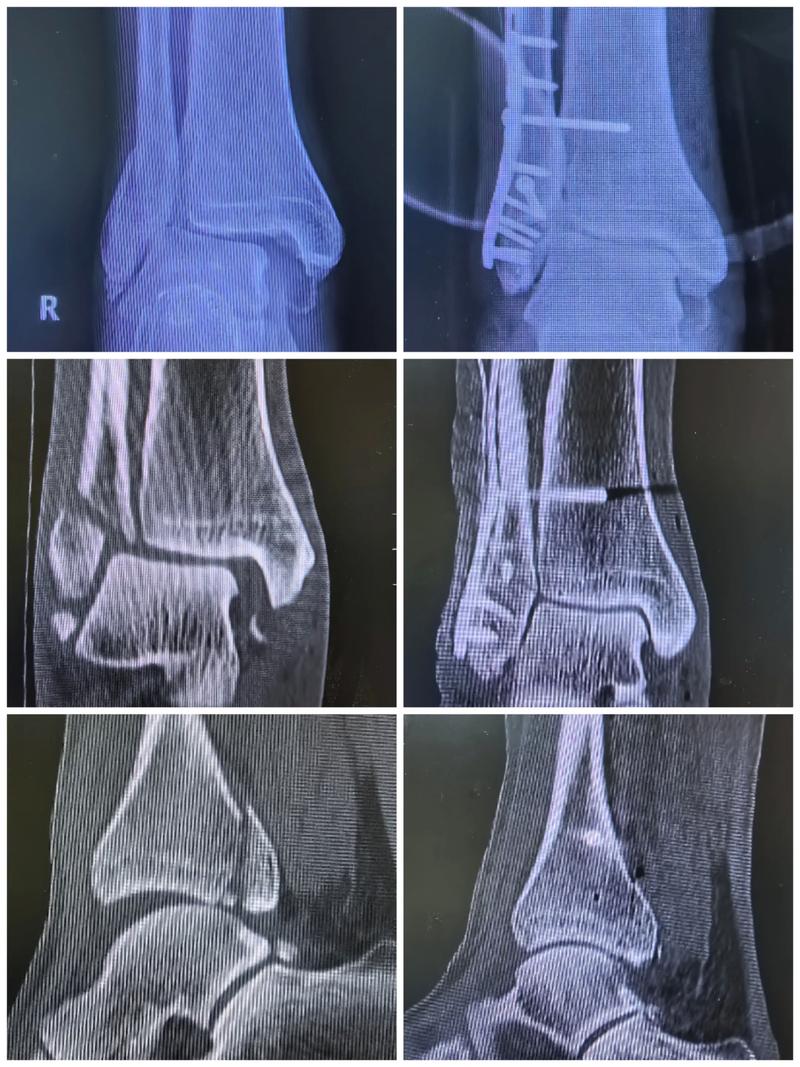

体育资讯4月3日讯 据名记Michael Scotto报道,老鹰中锋兰代尔遭遇右脚高位踝关节扭伤,预计将在约两周后重新接受评估。

兰代尔本赛季为亚特兰大出战了23场比赛,场均上场19.4分钟,贡献9.1分4.1个篮板,投篮命中率为51.6%,三分命中率为39.1%。